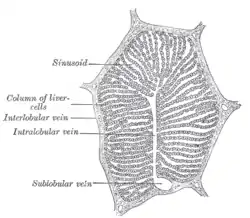

A single lobule of the liver of a pig. X 60. (Central vein not labeled, though region is visible. Central vein would be a single vein at the center of the lobule.) | |

In microanatomy, the central veins of liver (or central venules)[1] are veins found at the center of hepatic lobules (one vein at each lobule center).

They receive the blood mixed in the liver sinusoids and return it to circulation via the hepatic veins.[2]

The circulation of venous blood is: portal vein (which is formed by the joining of the superior mesenteric vein with the splenic vein) drains into the sinusoids of the liver, these all drain into the central veins of liver which drain into the hepatic vein to be returned to IVC.